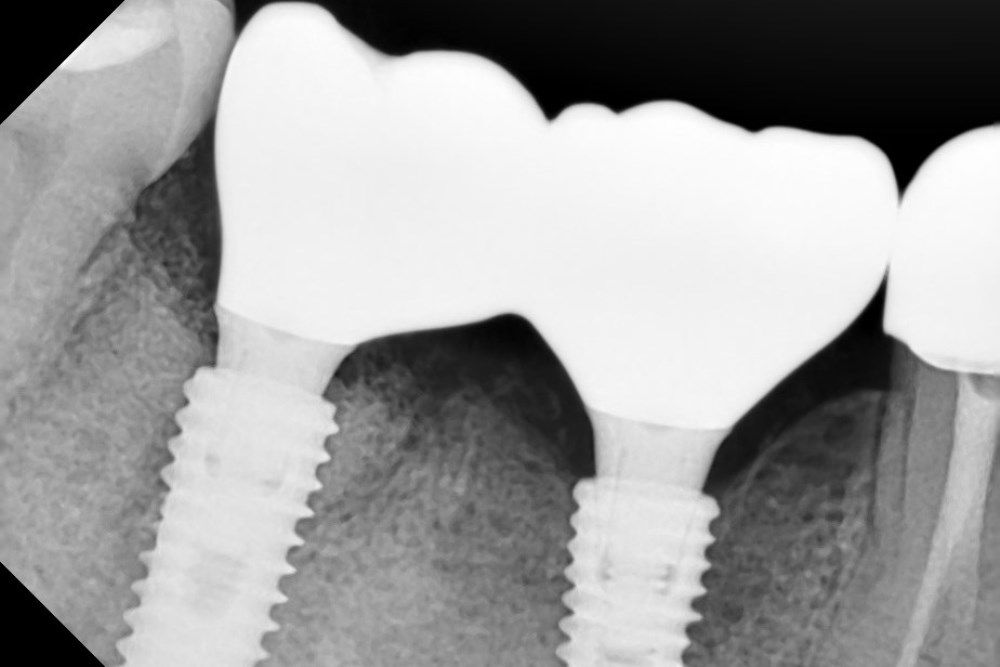

рентген имплантатоы